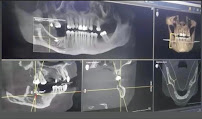

I had a very good experience at this clinic. The staff is highly professional, friendly, and always ready to help. The service was fast and very accurate, and the environment was clean and well-organized. What impressed me the most is the use of the latest technology, especially the 3D imaging service, which has been missing in our city for a long time. This shows a high level of investment and dedication to providing quality healthcare services. I highly recommend this clinic to anyone looking for professionalism, accuracy, and modern imaging technology.

The best radiology clinic in the city. Quality service and qualified staff. 3D scanner, the service that the city was missing. I highly recommend it.

Quality service and correctness. A caring and very polite staff. The dental scanner is a very valuable aid in dental services.